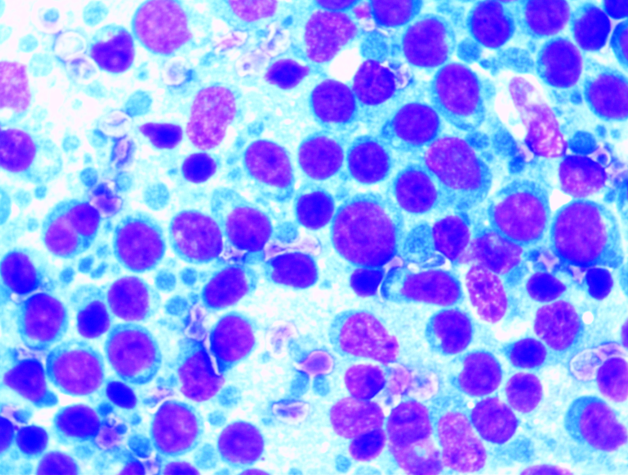

조직검사

병변의 조직을 재취, 재취된 검체를 현미경으로 관찰하여 병변을 진단합니다.